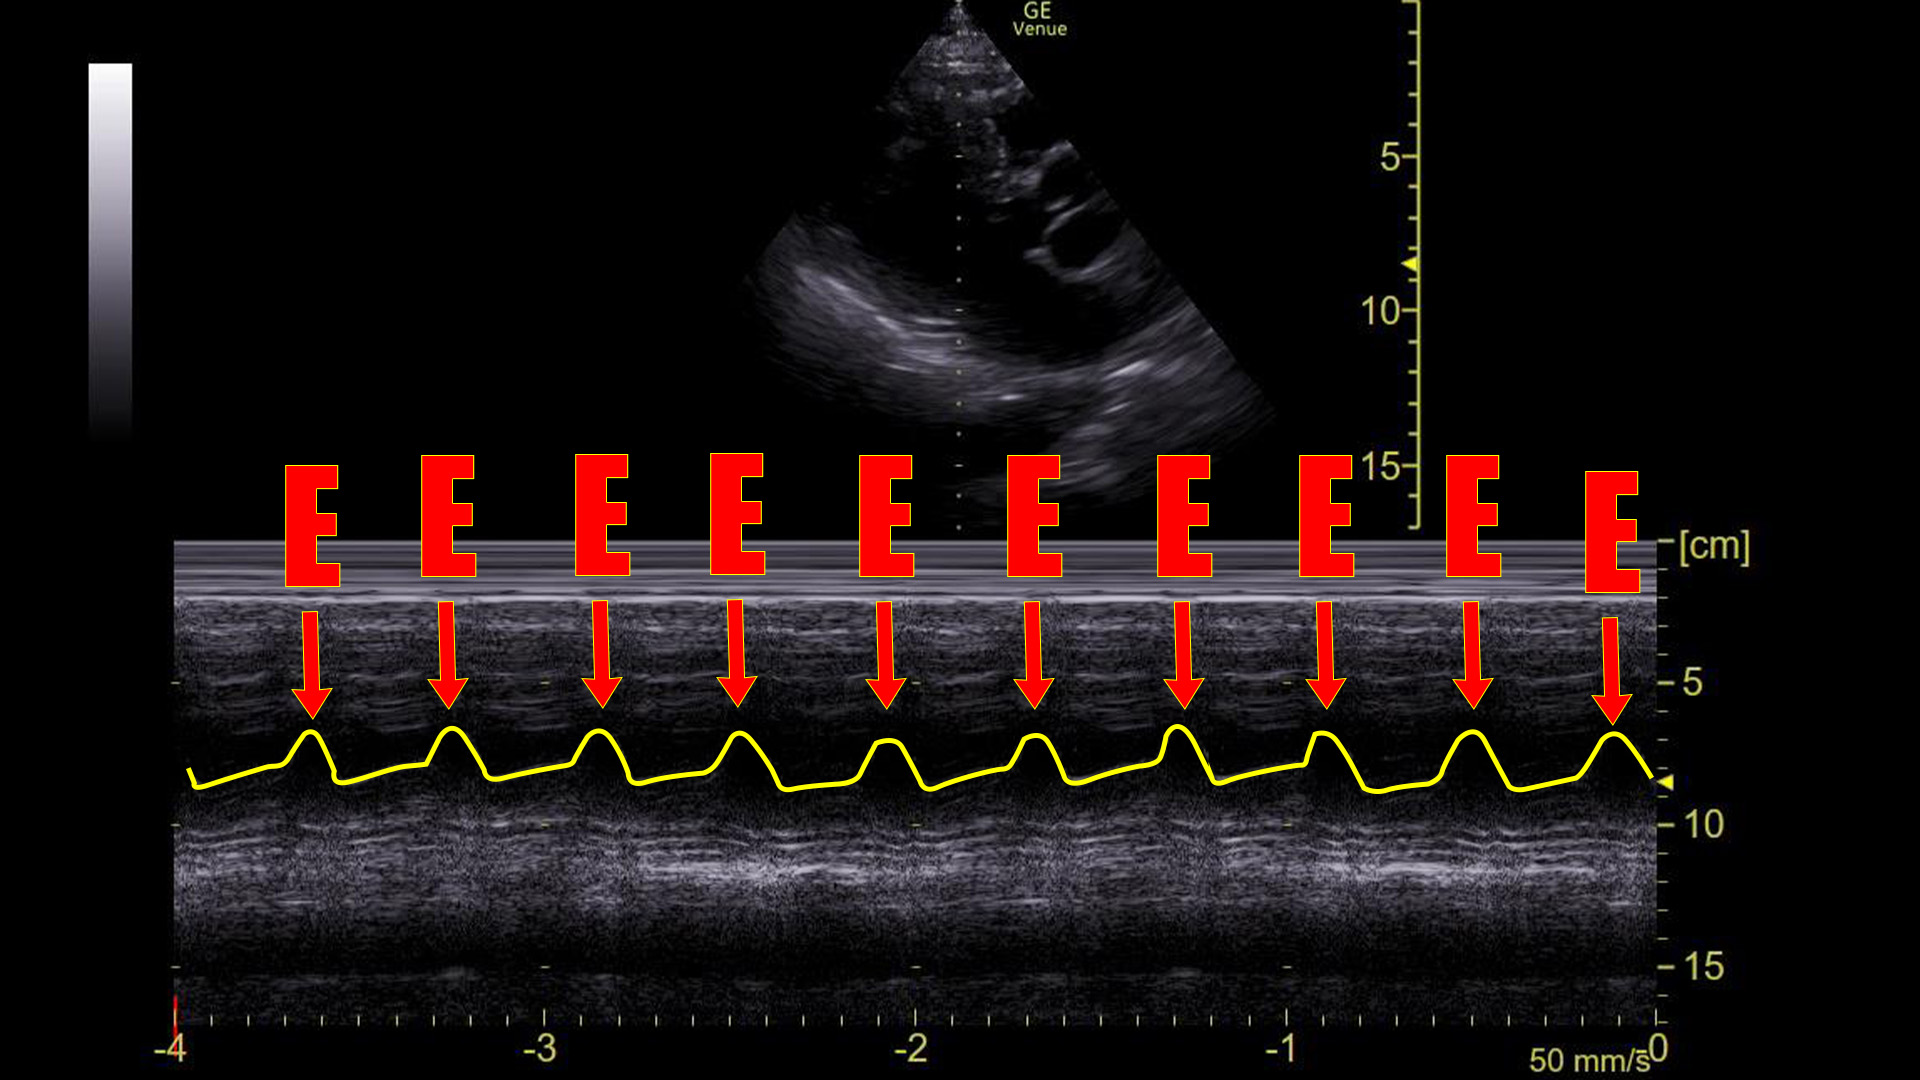

Given the hypotension and the fact that he did not respond to fluids, we cardioverted him. Here is the same tracing after the cardioversion:

Adding the same highlight as above:

Here we see there are two flaps of the mitral valve with every beat of the heart, which is what we see in sinus rhythm. Indeed, the patient was in sinus after the cardioversion and his blood pressure normalized immediately.

The point is, that in a sinus rhythm, the mitral valve opens not once, but twice for every contraction: Once during ventricular relaxation (passive ventricular filling) and a second time during atrial contraction.

We can see this on ultrasound as demonstrated above. Graphically on the screen, the first movement is called the E-wave, and the second is called the A-wave.

In a sinus rhythm, we see E-waves and A-waves. This is a normal appearing tracing.

In a sinus rhythm, the mitral valve opens twice during ventricle filling: once during passive filling, then again during atrial contraction. We can see these two movements on an M-mode tracing with the spike placed through the anterior leaflet of the mitral valve on a parasternal long axis view of the heart. Graphically, the first movement produces a wave that is termed the E-wave; the second is the A-wave. Absence of the A-wave tells us that there is no atrial contraction, which would be seen in conditions like atrial fibrillation, SVT, atrial flutter, or ventricular rhythms.